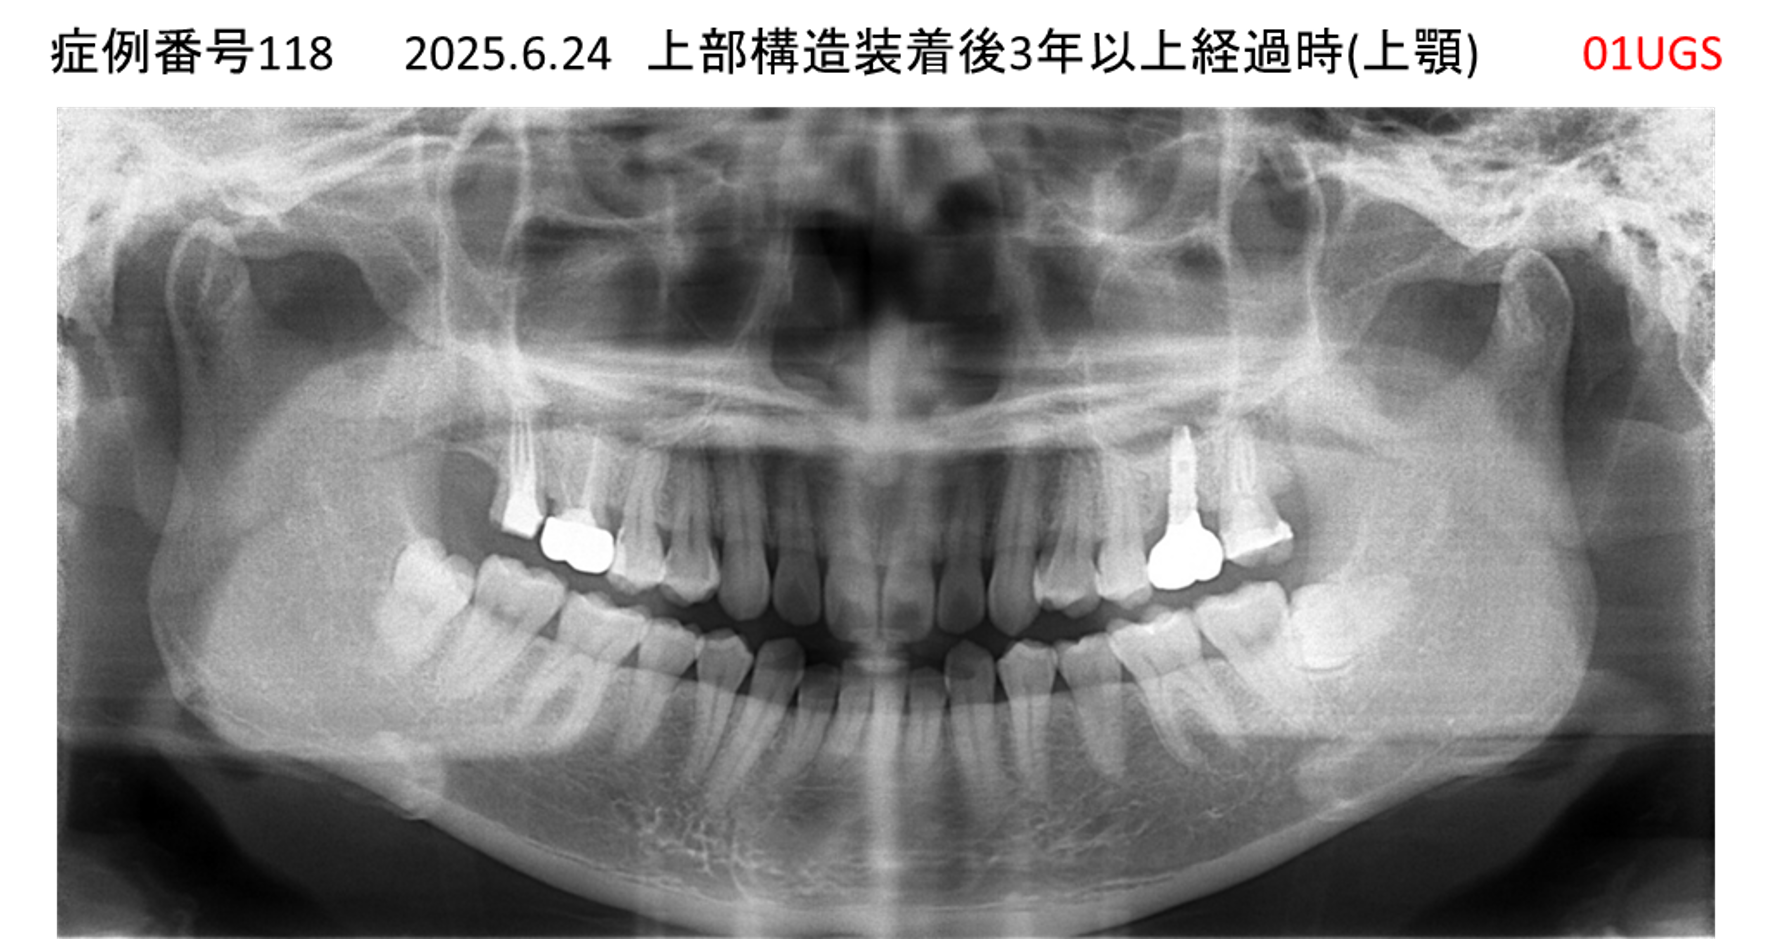

奥歯で噛めない患者様のインプラント症例

| 治療名称 |

インプラント |

| 治療費用 |

365万円+税 |

| 治療期間 |

5か月 |

| 患者さんの症状(主訴) |

奥歯で噛めない。上の前歯が揺れてきた。 |

| 治療内容 |

抜歯即時インプラント |

| 治療結果 |

食事に困らない。見た目がとても良くなった。 |

| 治療の注意点(リスク/副作用) |

インプラントが壊れたら再治療が必要 |